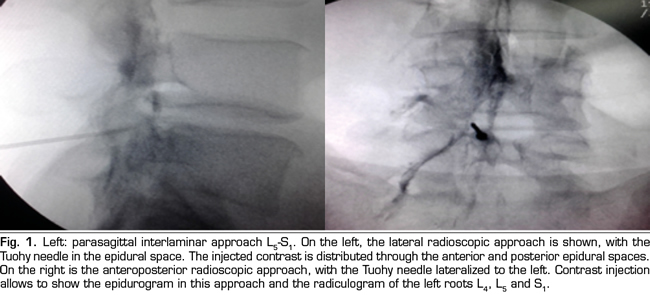

Figure 1

Figure 2